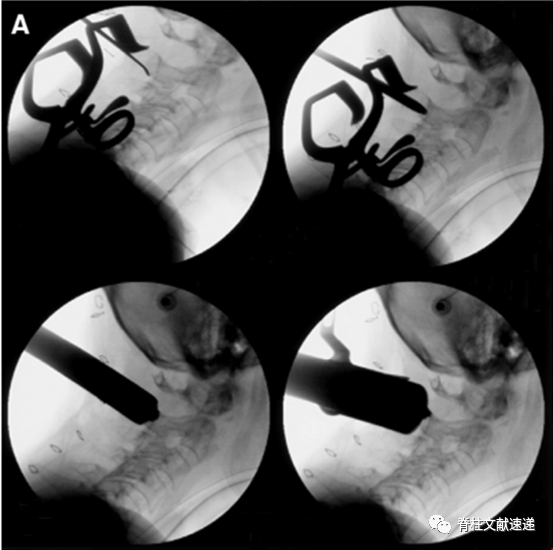

作者先在4具新鲜冰冻尸体进行模拟,然后将这一技术应用于5例患者,主要手术步骤如下。

1)颈后中线旁开2.5cm做纵行2.5cm皮肤切口。钝性分离软组织。

2)放置初级扩张通道在C2关节面最高点。逐级扩张,然后置入可扩张工作通道。

3)将工作通道向上倾斜,显露C1后弓、C2椎板和峡部,C1/2侧块间隙,使用明胶海绵和双极电凝止血,必要时牺牲C2神经根。

4)处理C1/2侧块间隙并植骨,然后按照标准技术置入C1侧块螺钉和C2椎弓根螺钉。在置入C2螺钉时,工作通道需要较大头倾角。

5)安装连接棒。

上图:(a)显示颈部皮肤标记和皮肤的伸展性,术中透视图像,显示最初扩张通道在C-2关节面(b),逐级扩张(C),放置可扩张工作通道(d),在C-1侧块用手钻做钉道(e)和最终内固定情况(f)。